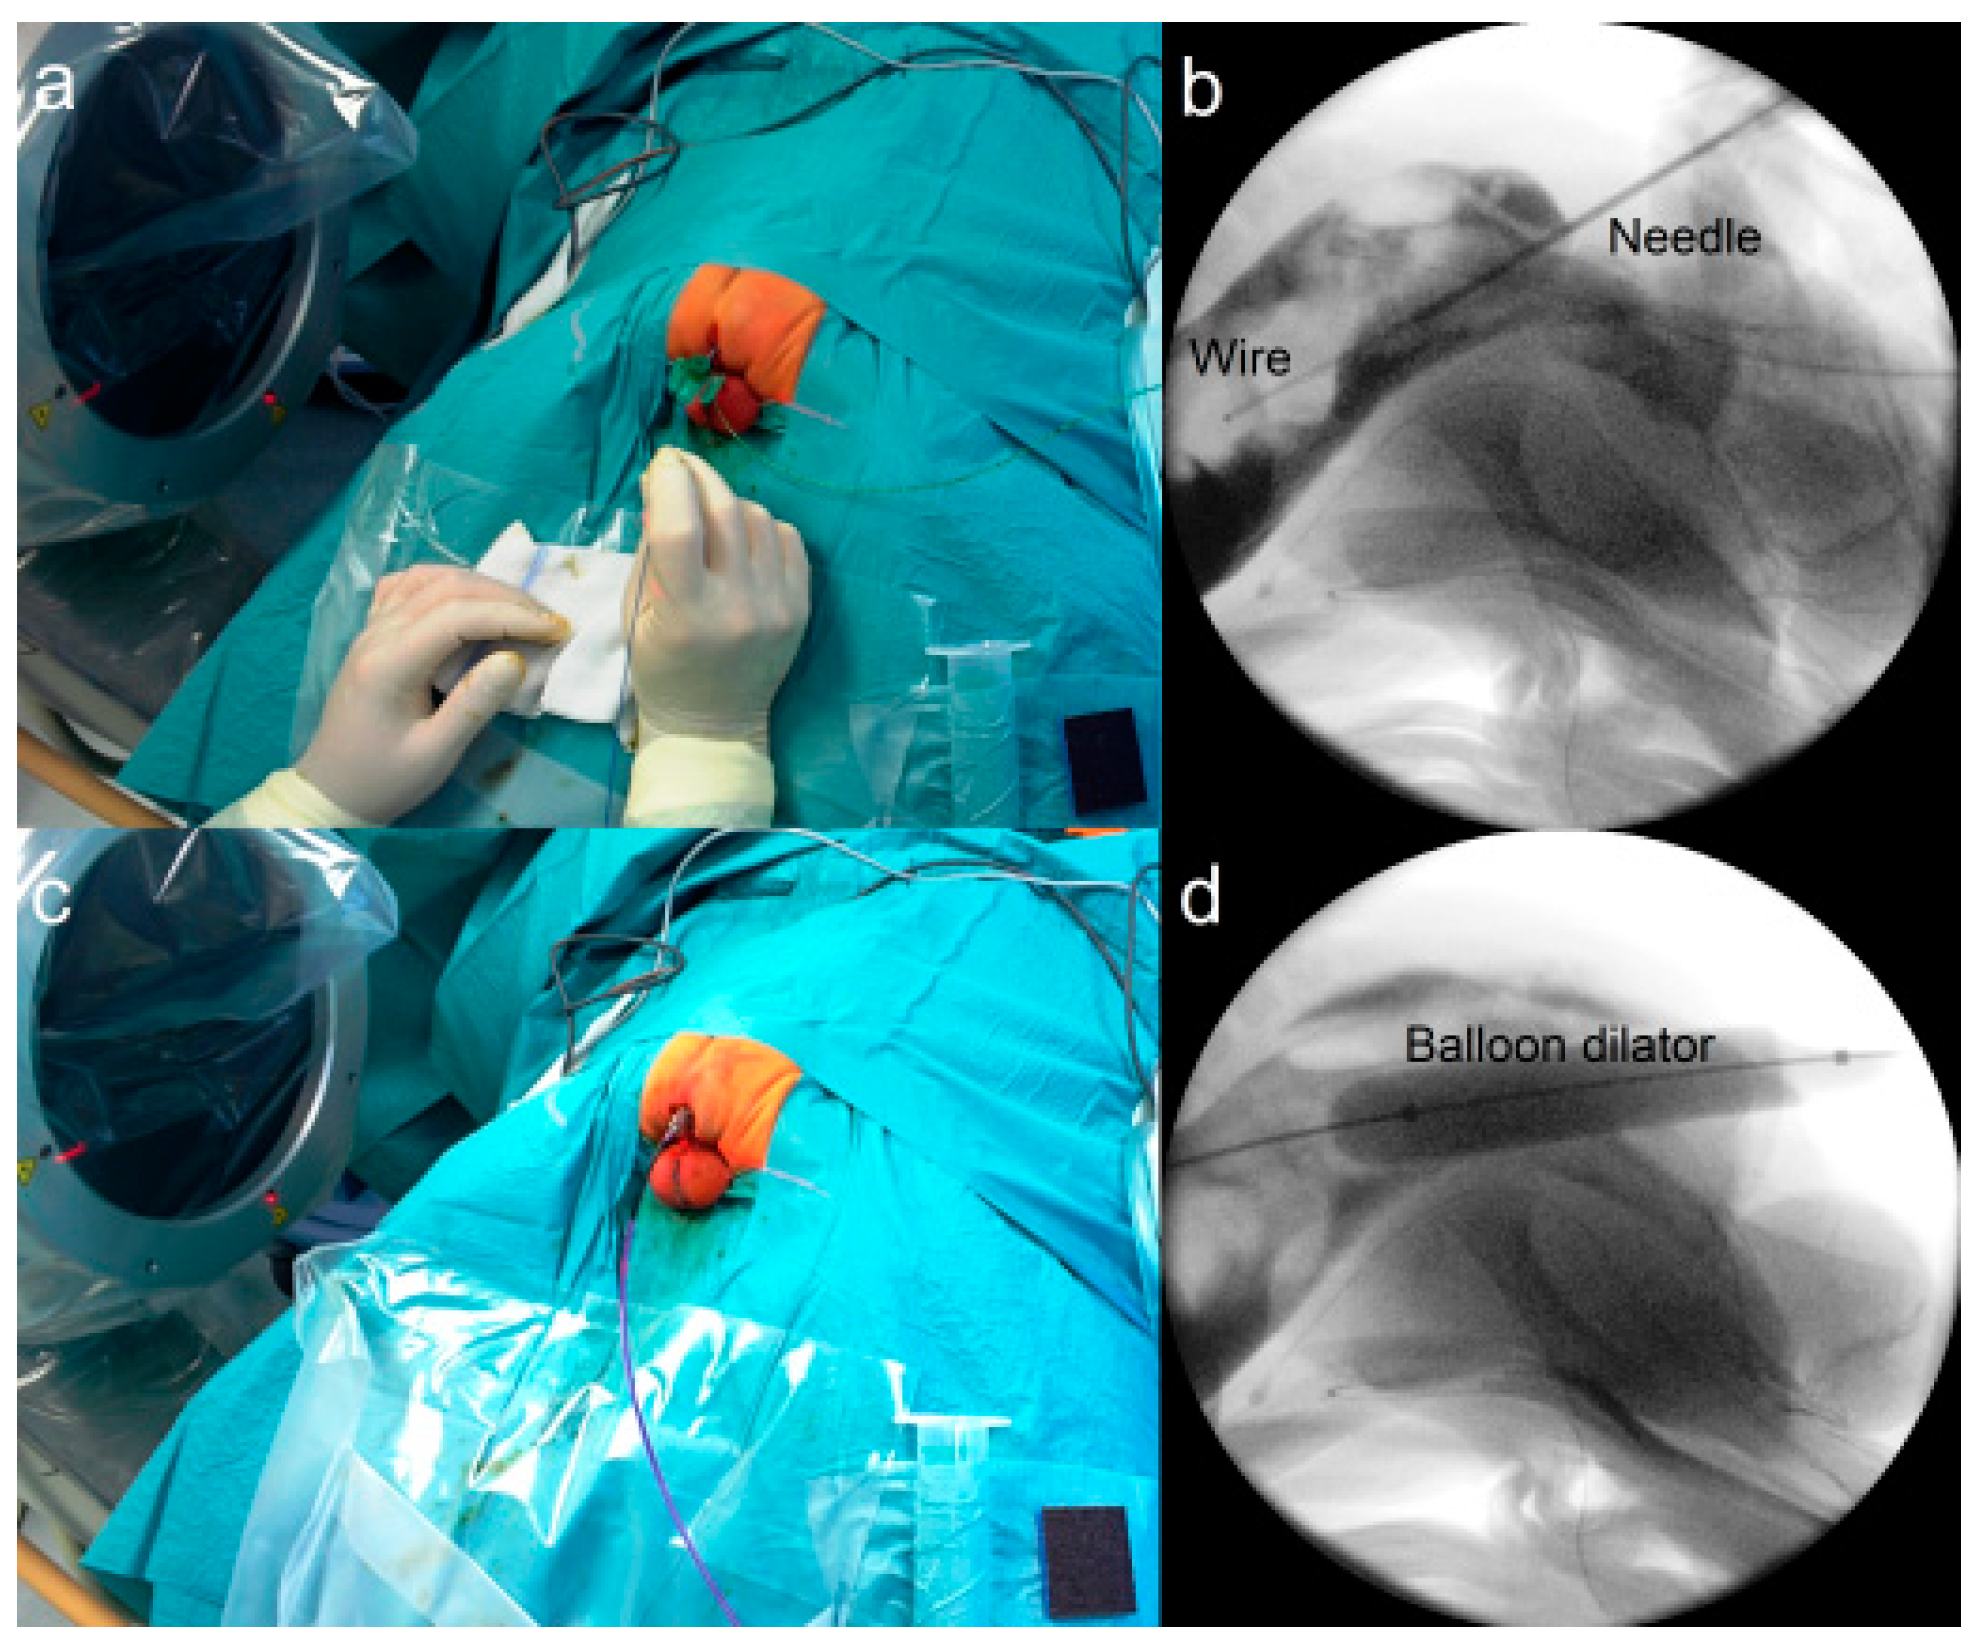

2.3.3. Fluoroscopy-Guided (Interventional) PARP (iPARP)